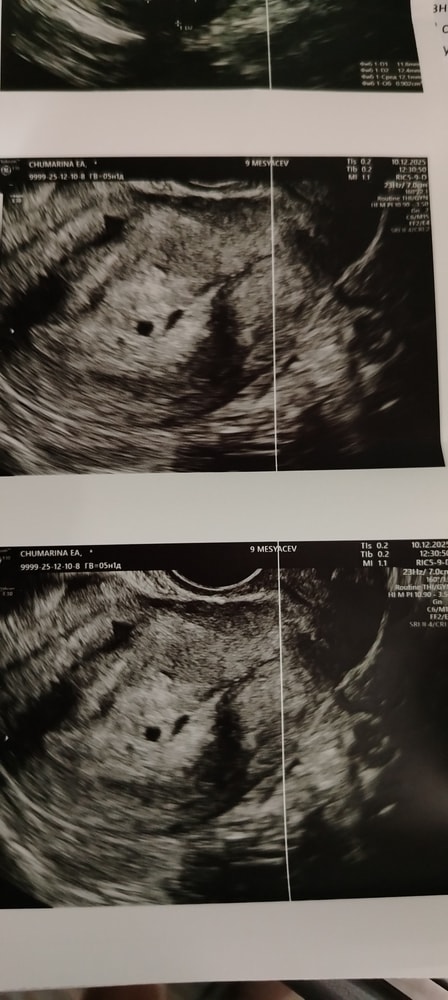

Подскажите пожалуйста задержка тесты положительные сделала узи поставили под вопросом беременность срок по узи 5 недель 1 день.

Это 2 плодных яйца или одно нашли?

Вероника, ну да подожду 10 дней потом схожу на УЗИ ещё раз. По фото только не понятно что там два или один

Так видно беременность

А в чем переживания? Не совпадает срок? Ну судя по тому, что вы только недавно обнаружили задержку, то радоваться надо) ПЯ в матке.